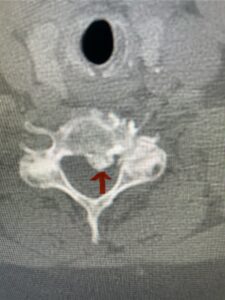

Another patient, a 77 year-old female, presents with pain, numbness, and weakness of her arms and difficulty with balance over a 6-month period. MRI revealed severe osteophytic disease at C5-C7 with cord compression (Fig. 4). Further work-up by fine-cut cervical CT to evaluate the nature of compression revealed a completely calcified osteophyte (Fig. 5). Although the patient had a good lordosis and a posterior cervical approach would accomplish an adequate decompression, we elected to perform a two-level anterior cervical discectomy and fusion. This particular osteophyte is formidable because of its size but the compression was all anterior and would be a less invasive approach. Fortunately, during the procedure, the patient had a fair amount of osteoporosis which allowed the osteophyte to be drilled and bit away with considerable ease. Interestingly, the C6 7 osteophyte which was more a sheet of osteophyte was more challenging to remove. In the end the decompression went well, and we placed two interbody devices filled with bone graft with plates at each level (Fig. 6). The patient had a nice recovery with immediate reduction of pain and numbness. This case demonstrates the importance of recognition of cervical myelopathy in its early stages. A significant reversal of function is generally the rule if the patient has appropriate correlative findings on exam and MRI, particularly with long tract distribution weakness development within a year time period.

Fig 5a: Sagittal and axial cervical fine-cut CT scan demonstrating severe osteophyte formation causing cord compression at C 56 (red arrow)

Fig 5b: Sagittal and axial cervical fine-cut CT scan demonstrating severe osteophyte formation causing cord compression at C 56 (red arrow)